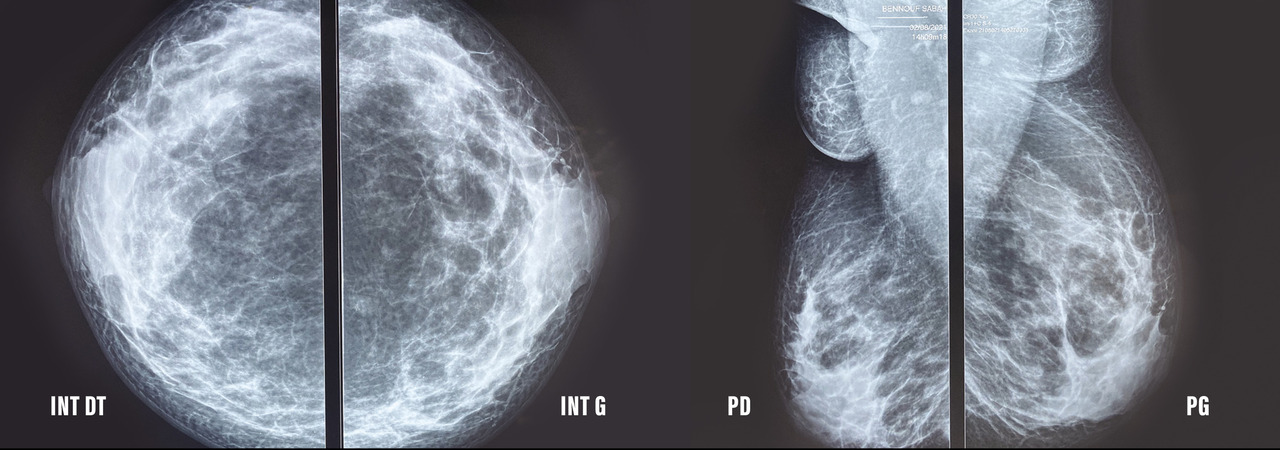

L’examen clinique révèle deux masses axillaires bilatérales, molles, bien limitées, de consistance glandulaire, indolores à la palpation, adhérentes au plan superficiel et mobiles par rapport au plan profond (fig. 1 ). Elles mesurent 5 cm sur 3 à droite et 4 cm sur 3 à gauche. La peau en regard est hyperpigmentée, sans individualisation de plaque aréolaire ou de mamelon. La mammographie (fig. 2 ) objective la présence de deux prolongements axillaires de tissu fibroglandulaire. Le complément échographique (fig. 3) révèle les mêmes résultats, concluant à des seins surnuméraires axillaires bilatéraux ACR2. Aucune lésion bénigne ou maligne n’est visualisée.

L’imagerie est primordiale pour la démarche diagnostique et le suivi. La mammographie révèle un aspect typique de parenchyme glandulaire mammaire de siège axillaire. À l’échographie, le diagnostic est évident lorsqu’une composante fibroglandulaire existe.6